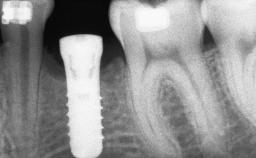

Staged bone augmentation of the alveolar ridge is indicated whenever a proposed implant site is deficient and will not support implant placement with simultaneous grafting. This is particularly true of healed sites presenting with facial flattening of the ridge. Since primary stability cannot possibly be achieved in this situation, it is recommended to use a staged approach with guided bone regeneration (GBR) for correct three-dimensional placement of the implant. In the anterior maxilla, staged GBR procedures are conducted not only to provide adequate bone volume for implant placement but also to restore a proper and stable contour of the orofacial ridge for improved long-term esthetics. A case is presented that demonstrates the technique for single-tooth replacement utilizing a staged approach with a particulate grafting material. A 50-year-old man whose tooth 11 was missing presented for consultation to the Center for Implant Dentistry in January 2010.

Bone Volume Deficient horizontally, requiring prior grafting